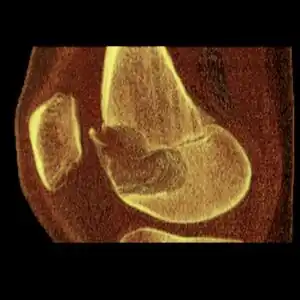

Osteochondroma, a common type of non-cancerous chondrogenic tumors

Osteochondroma[2]

Chondroblastoma[2]